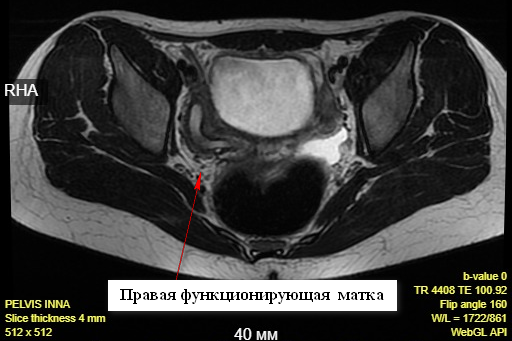

Примером командного подхода специалистов роботического центра, урологов и гинекологов является случай успешного хирургического лечения 14-летней девочки с сочетанным пороком мочеполовой системы. У пациентки отсутствовала правая почка, что сочеталось с удвоением матки, при этом правая матка функционировала и имела шейку, а левая была в виде мышечного валика без признаков функции, влагалище отсутствовало (агенезия). Результатом стало скопление крови в полости функционирующей матки и в ее шейке. Менструальная кровь, не имея выхода наружу, забрасывалась через маточную трубу в брюшную полость. В результате девочка страдала от невыносимых периодически возникающих болей в животе.

Установить диагноз помогло проведение МРТ малого таза. Стало понятно, что оперативное лечение было единственным вариантом лечения пациентки. Обратившись в отделение гинекологии для подростков Детского лечебно-реабилитационного комплекса Центра Алмазова, родители девочки задавали вопрос о возможности проведения операции, которая могла бы сохранить возможность менструаций и репродуктивной функции. Консилиум в составе директора Института перинатологии и педиатрии д.м.н. Т. М. Первуниной, заведующего отделением д.м.н. Н. А. Кохреидзе; заместителя главного врача по онкологии д.м.н., профессора Э. В. Комличенко; руководителя НИЛ детской хирургии врожденных пороков развития д.м.н., профессора И. М. Каганцова и заведующего кафедрой урологии с курсом роботической хирургии, руководителя центра роботохирургии д.м.н., процессора М. С. Мосояна заключил, что такую возможность может обеспечить проведение роботической операции.